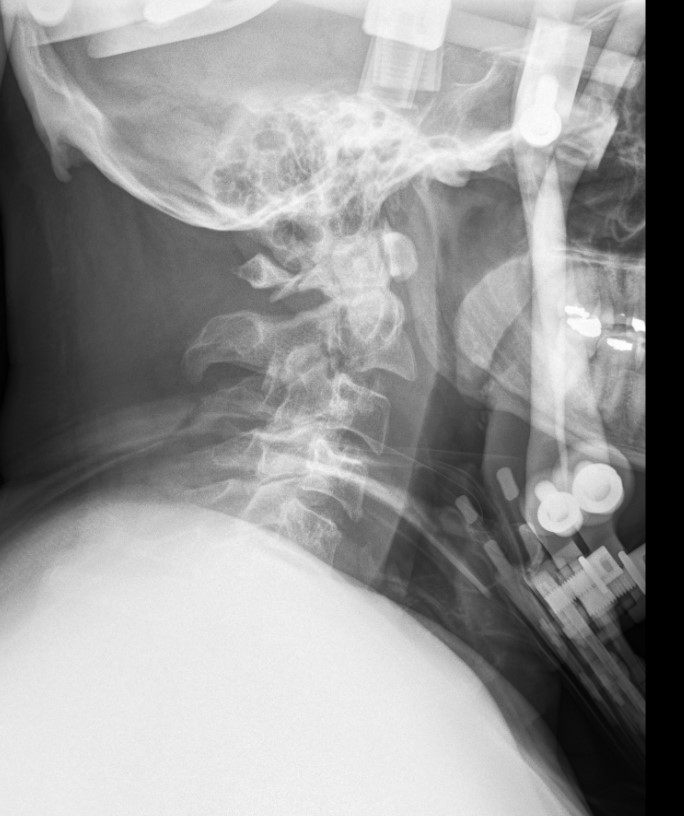

Hangman's fracture reduced and held in halo-vest

Post halo flexion and extension views demonstrating fracture stability